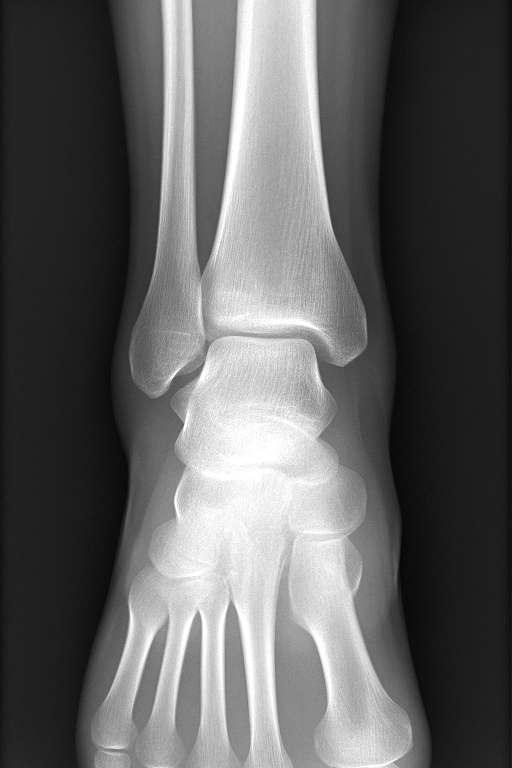

L'articulation de la cheville est composée de trois os principaux :

- le tibia et la fibula (péroné) formant la mortaise tibio-fibulaire,

- et le talus (astragale) qui s'articule avec eux.

- Radiographies standards : pour exclure une fracture associée,